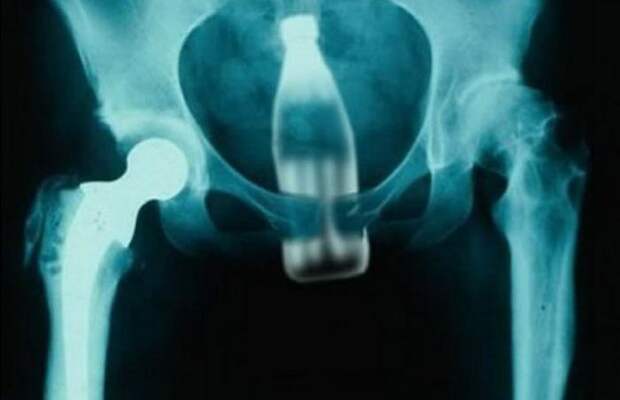

5. КОКА-КОЛА – ВЫПЕЙ И УЛЫБНИСЬ!

Кока-Кола – широко известный бренд безалкогольного напитка. Эта компания – абсолютный монстр. Люди по всему миру любят пить Кока-Колу, которая продается в различной упаковке - банках, пластиковых и стеклянных бутылках.

60-летний мужчина обратился в больницу и сначала пожаловался на запор. Затем, после того как обнаружилось, что в его заднем проходе застряла целая бутылка Кока-колы, он пожаловался, что воры засунули бутылку в его анус. В больнице врачи использовали вакуум и вытащили бутылку. У нас только один вопрос – это диета или регулярность?